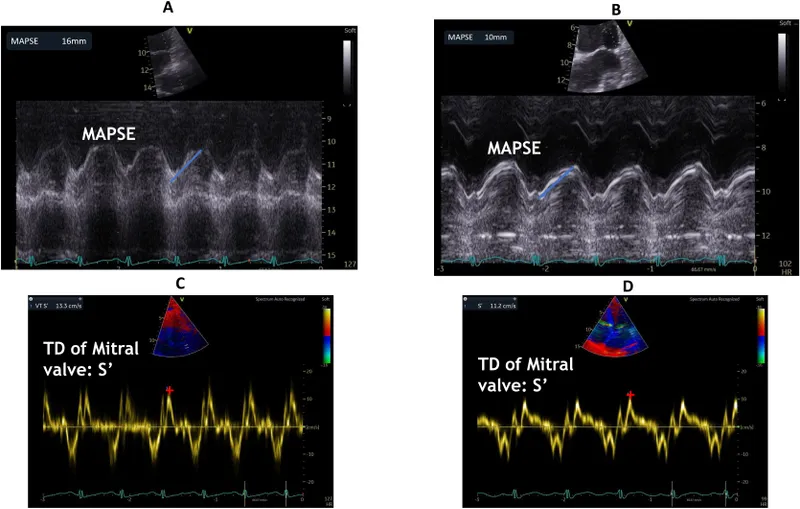

💡 Master This: Sepsis-induced cardiomyopathy occurs in 40-50% of septic shock patients, with reversible myocardial depression showing ejection fraction <45% that typically recovers within 7-10 days with appropriate treatment

| Heart Failure | 40-70% | Valve destruction | Dyspnea, pulmonary edema | Echocardiography | Diuretics, valve surgery |